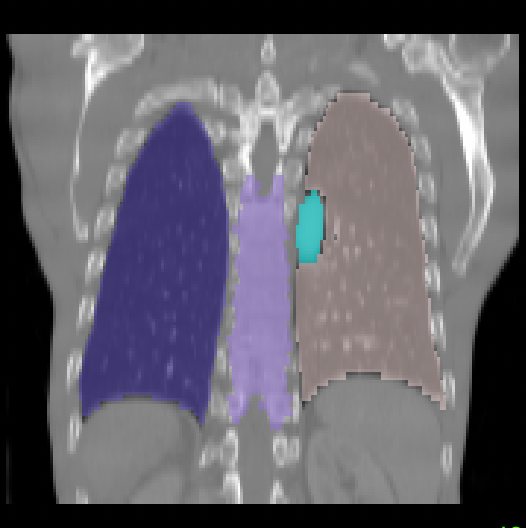

To better understand the performance of different deformable registration methods, we display organ-specific results in Fig. 3 and Fig. 4. For conciseness, in the head & neck CT dataset, we average the DICE of left and right organs into one score and calculate the median and interquartile range of DICE within each organ. In the chest CT dataset, we divide the 35 organs into 9 groups and calculate the median and interquartile range of DICE within each group. It is observed that SAM-deform surpasses other methods in 13 out of 17 organs or organ-groups. Some organs such as len, nerves, arteries and veins display lower DICE for all methods, this may be because they are typically small or easy to be confused with surrounding tissues. Qualitative examples are also shown in Fig. 5 with a clearly improved alignment of various organs after registration.

| Moving | Fixed | Second best | SAME++ |